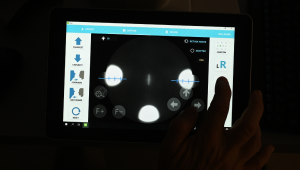

Великий сенсорний екран 10,1 дюйма

Сенсорною панеллю легко керувати. Деталі зображення можна побачити та перевірити більш детально та точно через великий екран.

| Вирівнювання | Повністю автоматичне 3D відстеження | |

| Режим вирівнювання | Повністю автоматичний/ Автоматичний/ Ручний | |